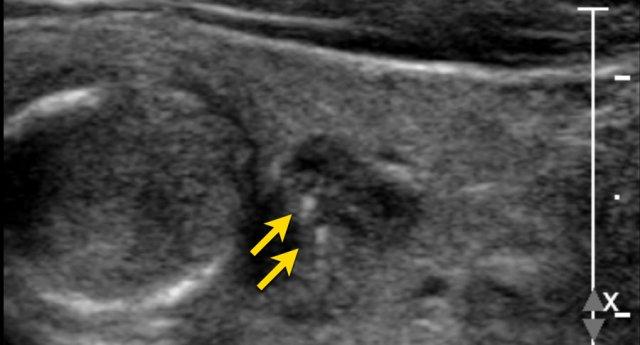

Nốt Không Rõ Ranh Giới

Trong hình ảnh được cung cấp, chỉ có các đoạn nhỏ của bờ nốt là có thể nhận thấy được (được chỉ ra bởi các mũi tên).

Phần lớn bờ nốt không phân biệt được với nhu mô tuyến giáp.

Điểm TI-RADS: 0 điểm.